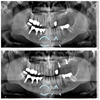

Implant tedavisi

Periimplantitis

Peri-İmplant Mukozitis